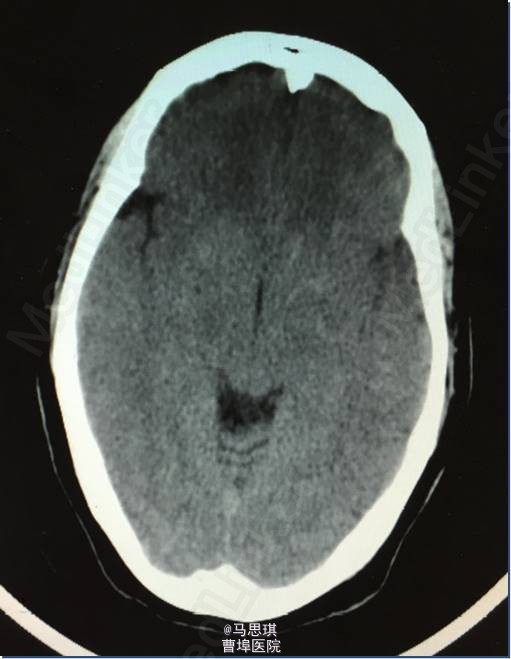

查体: PE:BP107/51 mmHg,双侧颈动脉未闻及杂音,双肺(—),心率80次/分,律齐,各瓣膜听诊区未闻及病理性杂音,腹(—),双下肢不肿。 NE:神清,部分性混合性失语,右侧轻度中枢性面舌瘫,右上下肢肌力Ⅴ-级,左上下肢肌力Ⅴ级,感觉对称、存在,腱反射++,病理征(—)。NIHSS评分:2分。 实验室检查:血常规示:WBC 14.3*10^9/L,中性粒细胞 80.8%,PCT 0.32 ng/ml。大小便常规、肝肾功能、电解质、血糖、风湿因子、ESR、血液流变学、HCY、血气分析、D-二聚体、心损、免疫全套、凝血、甲状腺功能、肿瘤标志物、腹部彩超、胸片正常,HIV(—),梅毒(—)。 TCho:4.45mmol/L ,HDL-C:1.31mmol/L ,LDL-C :2.41mmol/L ECG:窦性心律,ST改变。 UCG:左房稍增大,左室舒张功能稍减低。 TCD:椎-基底动脉血流速加快。 颈动脉彩超:双侧锁骨下动脉粥样斑块形成(软斑)。 入院头部CT:大脑镰旁多发钙化灶;脑实质未见明显异常改变。

入院诊断为:“脑梗塞?” 患者有溶栓指征,但患者家属拒绝溶栓。 治疗: 氯吡格雷75mg Qd 拜阿司匹林0.1 Qd 立普妥 20mg qd 胞磷胆碱0.2tid 依达拉奉30mg ivgtt bid 康复治疗 入院第二天行MRI及MRA检查。 头部MRI:左侧额颞岛叶见片状稍长T2稍长T1信号灶,其内见较多增粗、增多血管影,原因?考虑:血管畸形所致左侧额颞岛叶缺血梗塞性改变?血管炎性病变或脑炎待排? 头颅MRA:左侧额颞岛叶见较多增粗、增多的血管影,右侧额颞顶交界区血管影稍增多。左侧胚胎型大脑后动脉。 入院第四天行头颅增强CT及CTA。 头颅增强CT:左侧颞叶见片状低密度影,其内见大小约0.7x1.6cm片状高密度影,与前片比较,见范围加大,考虑系梗塞后伴出血,血管畸形。增强扫描见左侧额颞叶较多迂曲扩张的血管影。 CTA:左侧额颞岛叶区域见大脑中动脉岛叶段,侧裂段及分叉段分支明显增多,部分迂曲、扩张,呈杂乱走行的血管团样改变,考虑血管畸形可能;右侧额顶交界区血管影稍增多。双侧颈内和基底动脉及大脑前中后动脉显示清晰,其大小、走行、信号未见确切异常,各血管壁光整,管腔未见确切狭窄,走行自然。 发现出血后,停用双联抗小板治疗,并加做DSA DSA示:左侧颈外动脉分支脑膜中动脉血管畸形,与颈内动脉,椎动脉无明显交通 修正诊断为: 左侧额颞岛叶脑梗塞并梗塞后出血; 左侧脑膜中动脉血管畸形 动脉粥样硬化症 上呼吸道感染